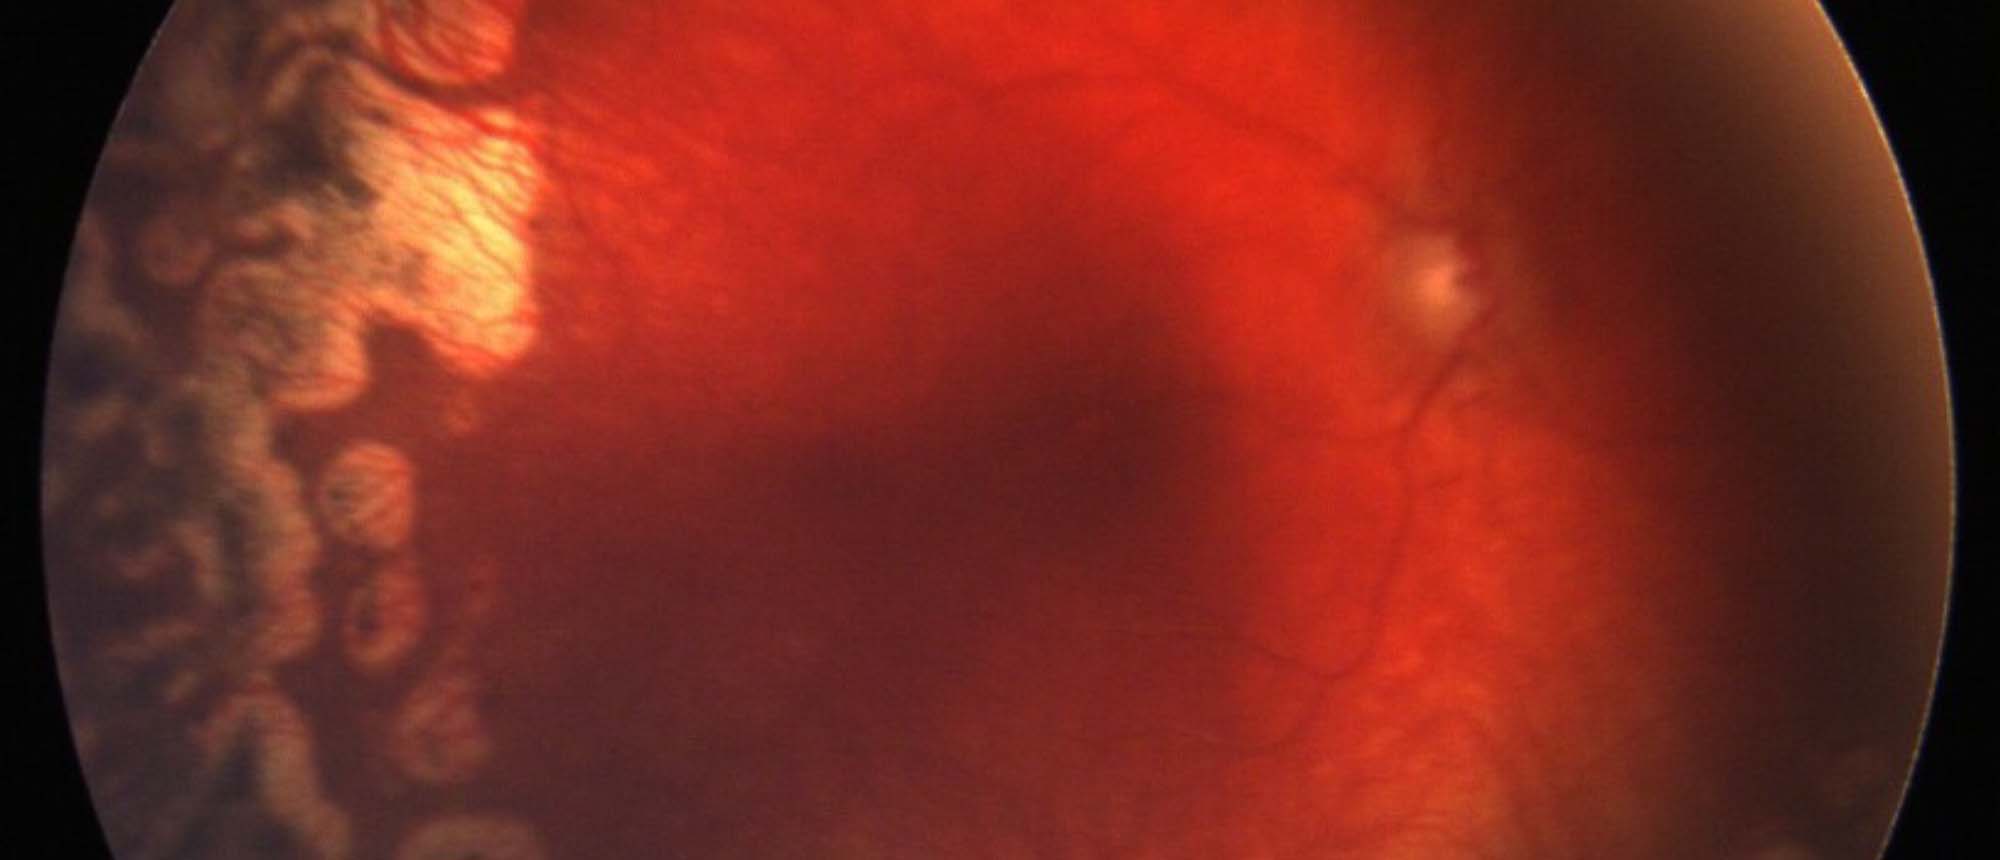

Abstract A patient with past ocular history of nonproliferative diabetic retinopathy presented for routine examination to retina clinic. Patient had no vision concerns nor any systemic symptoms on review of systems. On examination, patient found to have cream colored large calibre vessels diffusely…

Lipemia Retinalis A patient with past ocular history of nonproliferative diabetic retinopathy presented for routine examination to retina clinic. Patient had no vision concerns nor any systemic symptoms on review of systems. On examination, patient found to have cream colored large calibre vessels …